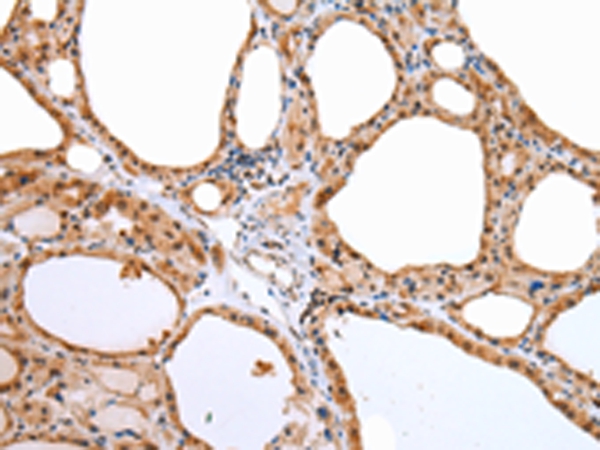

分类: 科研抗体货号: P43470别名: WEE1A; WEE1hu应用: WB,IHC反应种属: Human,Mouse,Rat